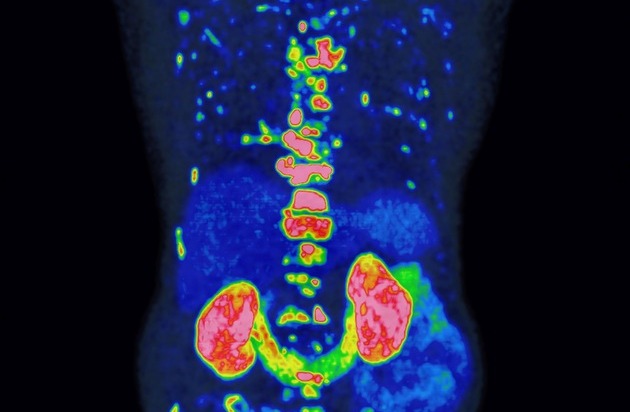

Das PROMISE-Team nutzte für die Risikobewertung die PSMA-PET**, ein hochmodernes Bildgebungsverfahren, mit dem sich Prostatakrebszellen besonders präzise und ihr Ausbreitungsstadium im Körper sichtbar machen lassen. Da die Methode empfindlicher ist als ältere Verfahren, mussten ihre Befunde zunächst in neue Behandlungsempfehlungen übersetzt werden – ein Prozess, den PROMISE maßgeblich geprägt hat. In einer der größten Studien weltweit wertete das Team Bilddaten von über 15.000 Patienten aus. Gemeinsam mit international führenden Forschungseinrichtungen entwickelte es daraus das PROMISE-Schema – eine Methode, mit der sich individuelle Risikoprofile auf Basis der PSMA-PET deutlich präziser bestimmen lassen. Darauf aufbauend entstanden Nomogramme, also Vorhersagemodelle für das individuelle Risiko, die für Ärzt:innen und Patient:innen verständlich aufbereitet und zur gemeinsamen Therapieentscheidung nutzbar sind.